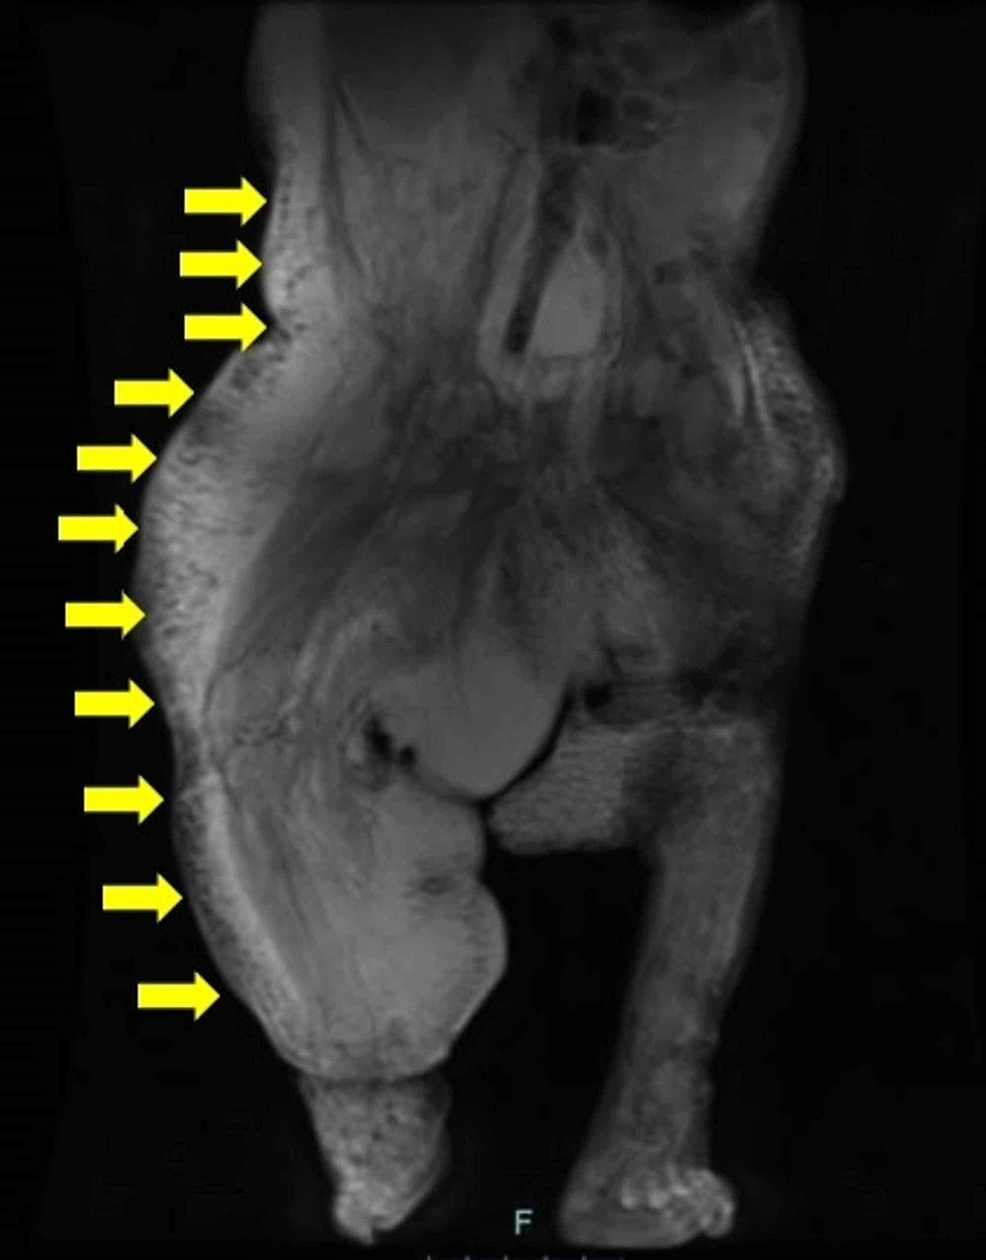

Hemimegalencephaly associated with CLOVES syndrome in a 2yearold boy Cloves Disease cloves is a rare overgrowth syndrome with complex vascular anomalies caused by a pik3ca gene mutation. cloves syndrome is a rare overgrowth condition with vascular anomalies and skin abnormalities. cloves syndrome is a rare condition that is primarily characterized by congenital overgrowth of fatty tissue; It affects various body parts, such as fatty mass, skin,. cloves. Cloves Disease.